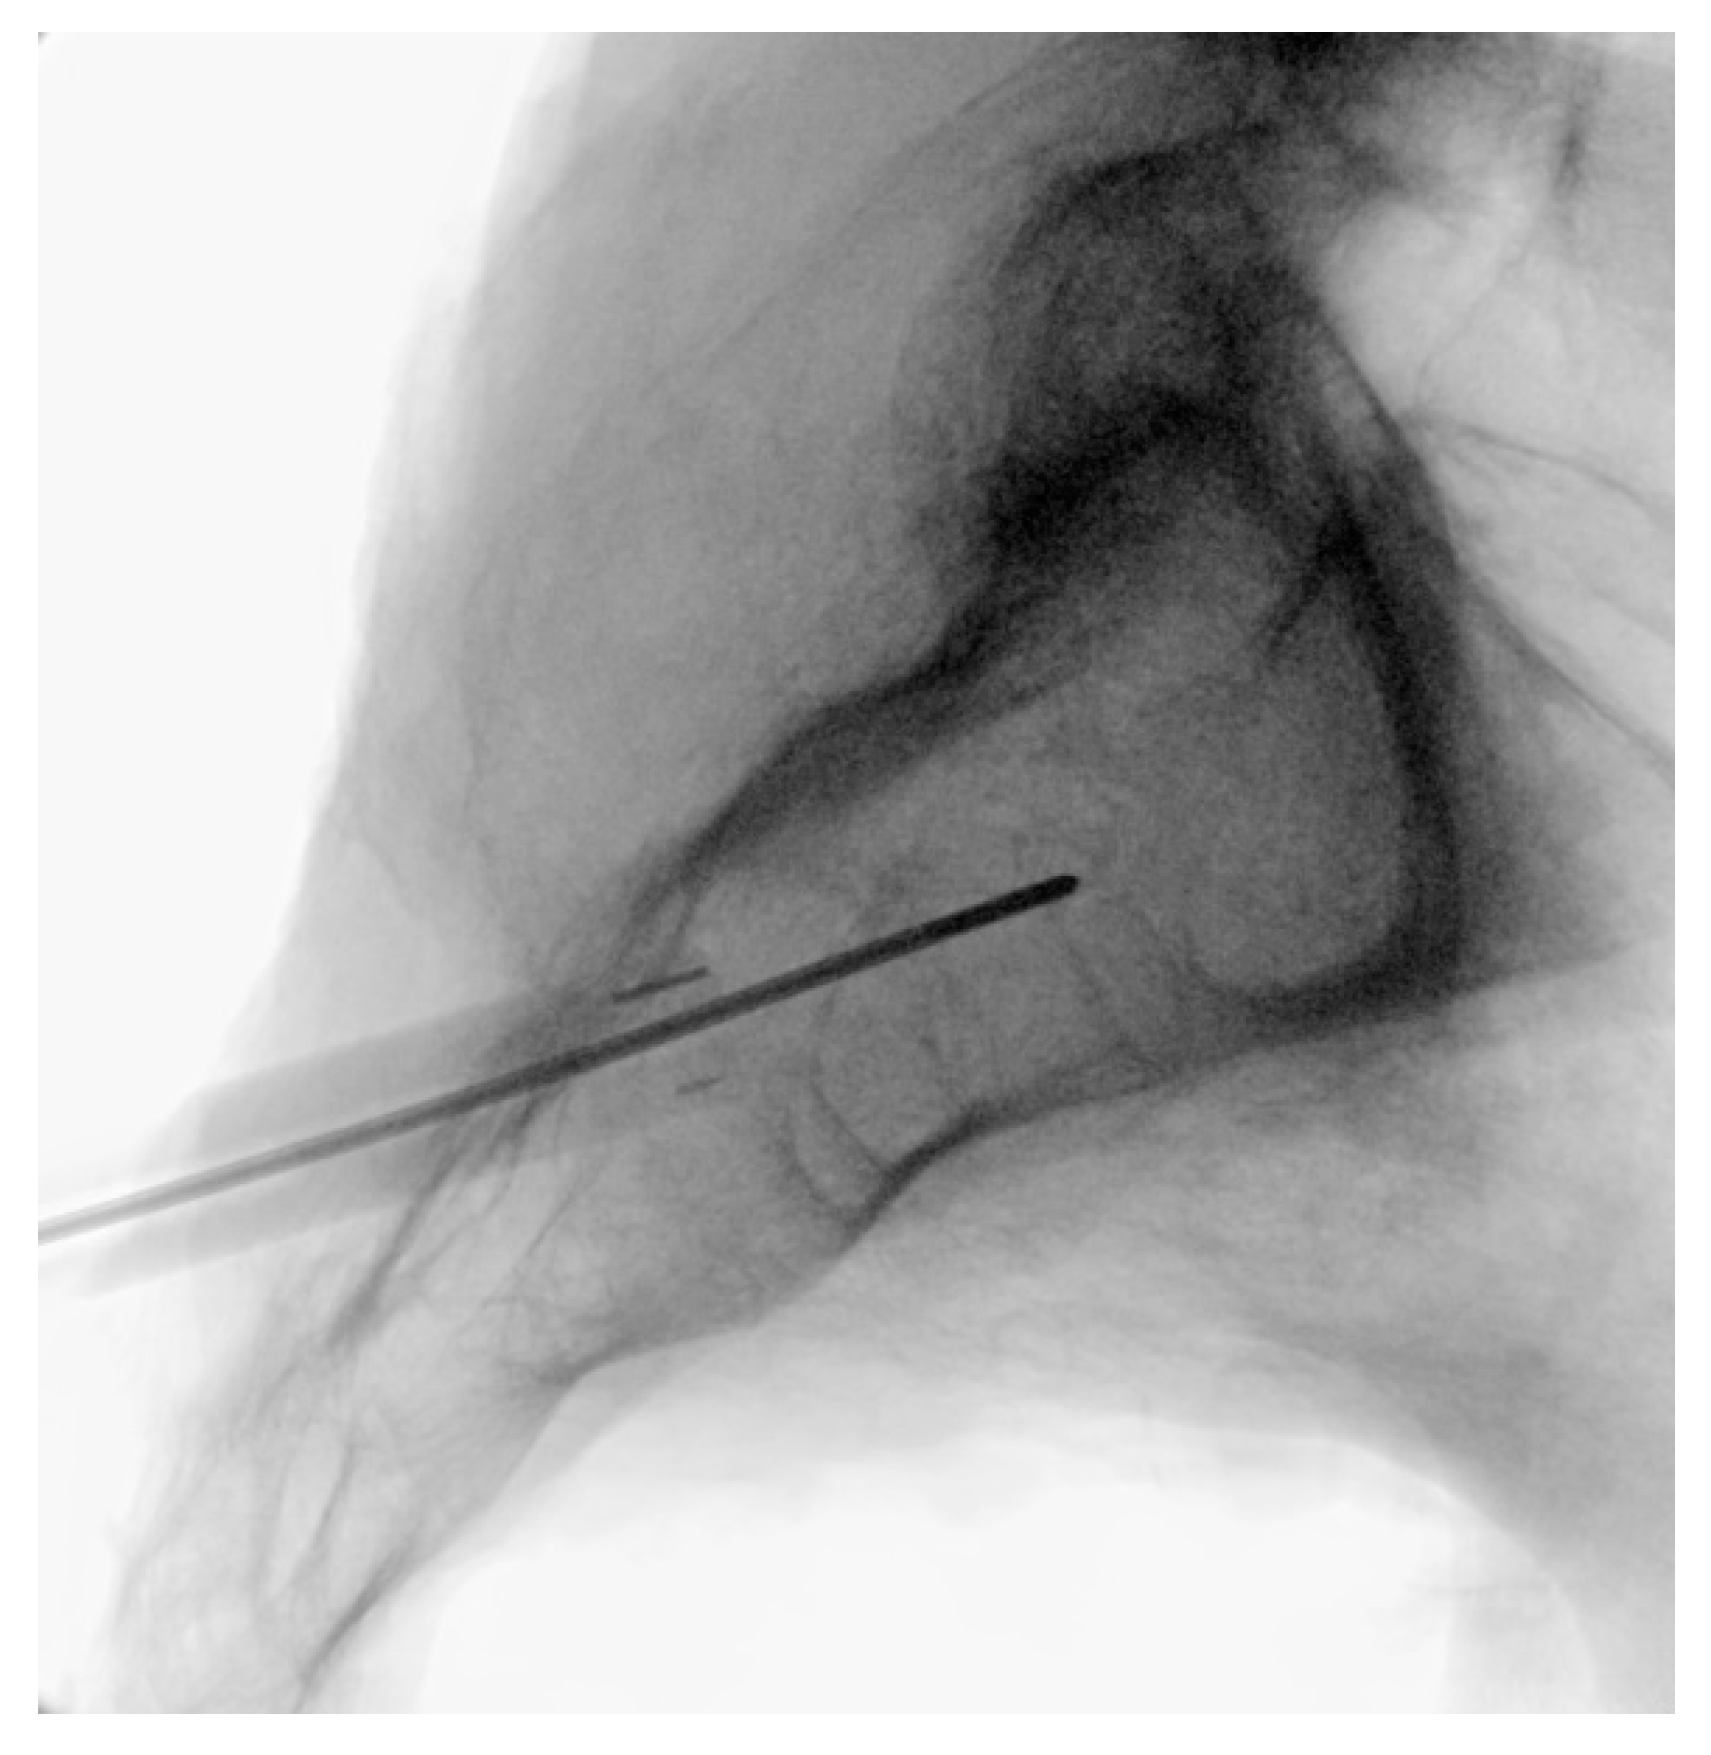

3.3.4. Steinman Pin Placement